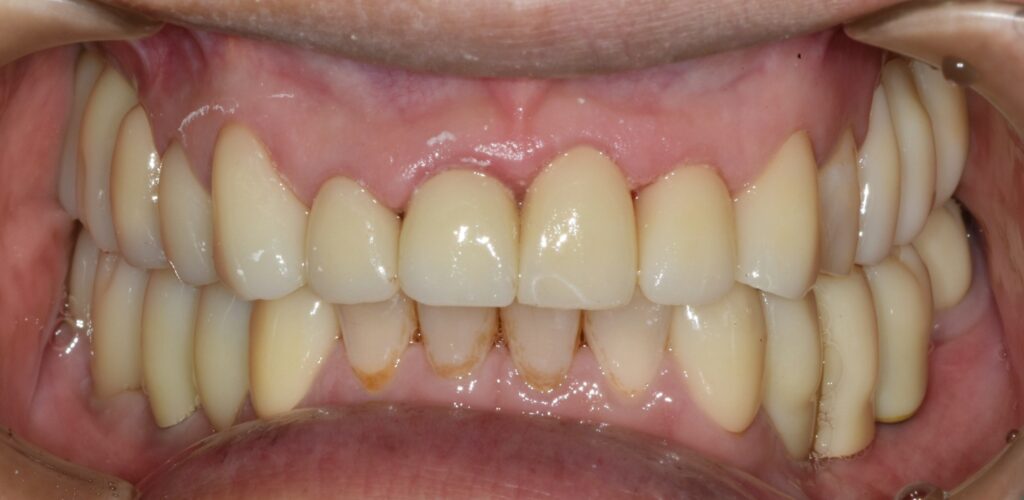

임플란트 식립 후 3개월 뒤에 임플란트와 뼈가 단단하게 붙은 것을 확인한 뒤 본을 떠서 임시치아를 만들었습니다.

1개월 동안 임시치아를 사용하면서 교합(치아가 물리는 관계)을 확인하고 모든 것이 편안해졌을 때 한 번 더 본을 떠서 최종 보철로 이행했습니다.

이렇게 임시치아 기간을 거쳐서 최종 보철을 완성하는 과정은 치료가 빨리 끝나길 바라는 환자분들도 힘드시겠지만 사실 저희 의료진도 힘들기는 마찬가지입니다.

하지만 임시 보철 기간은 반드시 가져야 합니다.

어금니가 없는 채로 3개월 이상 지내셨기에 턱관절이 새로운 치아에 적응하는 시간이 필요하며

또 지내시면서 음식물이 끼진 않는지 음식물이 잘 씹히는지 치아가 걸리지는 않는지 등 많은 부분에 대해서 미리 살펴보고 개선해야 할 점은 미리 개선하여

최종 보철물을 만드는 것이 가장 좋은 결과를 낼 수 있기 때문이죠.

위와 같이 치료가 완료되었습니다. 상당히 깔끔하게 잘 치료되었네요. 총 치료 기간은 4개월 소요되었습니다.